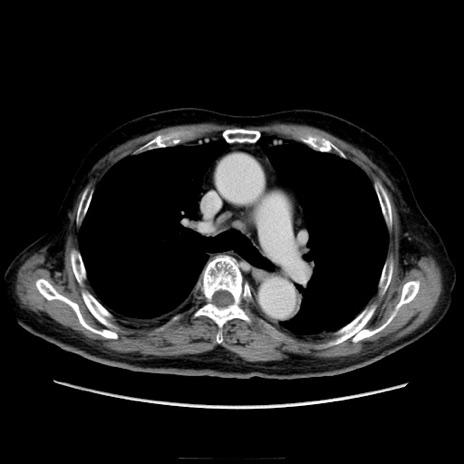

冠状断像

症例21(横断像)

【症例】70歳代男性

【現病歴】肝硬変・肝細胞癌にてかかりつけの方。約9時間前に食後より腹痛出現。症状が徐々に増悪し、嘔吐出現したため来院。

【既往歴】肝硬変、肝細胞癌(RFA、TACE後)